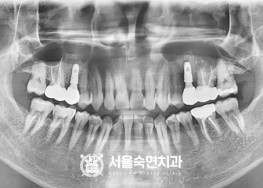

임플란트-치료-전후사진